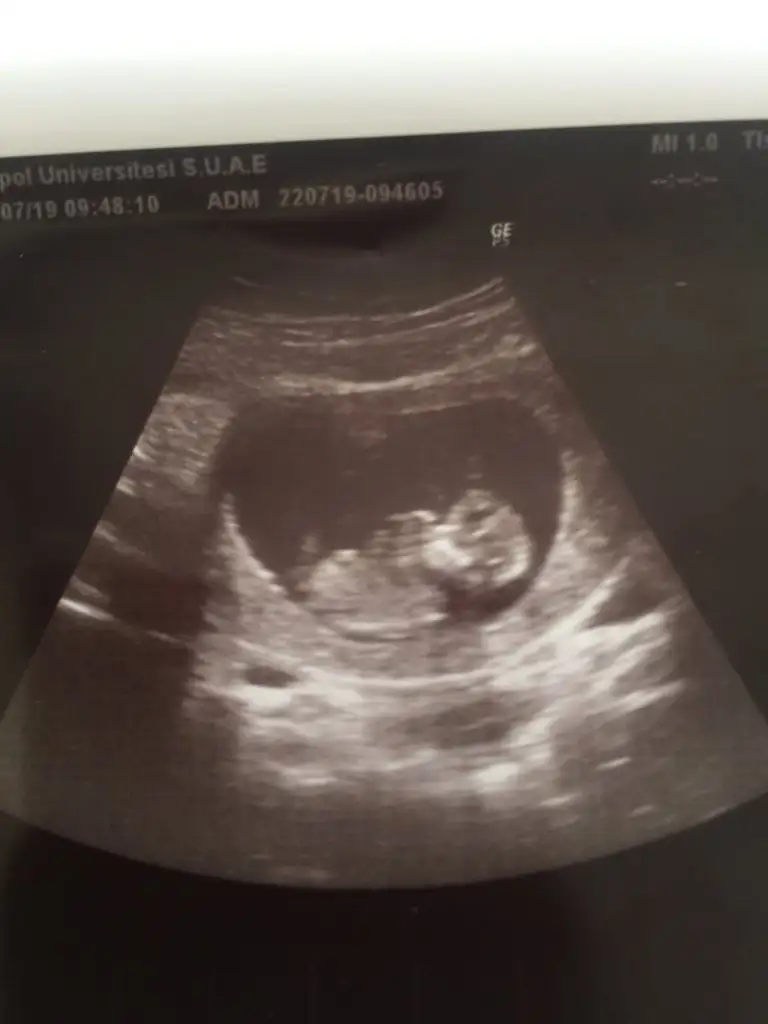

Bebeğin kız gibi☺

Teşekkür ederim yorumun içinKız diyorum

Banada 11 haftadada erkeğe benziyo dedi burdakiler, 12 hafta resimlerne daha yorum gelmediEvet hanımlar bebişime en çok kız yorumu gelmişti doktor erkeğe benziyor dedi 14+5 ken

Atsana bi usg ni cnm erkek dediyse değişmez benceAyyy olsun sağlıkla gelsinler de dünyaya ☺ Banda erkek dedi bende gördüm ama emin değil bu değişebilir dedi gönlümden geçende erkek tabi ama kesinleşsin istiyorumm

Erkek diyorum ikinci oğlumla usg aynı doktordan daha Emin’im banada dua edermisin hayırlı bi kız evladım olsun diye sağlıkla gelsin bebeğinBende yorum istiyorumm erkek demiştiniz 11 haftada buda 12+3

Valla canim ben yorum yaptigimi hatirlayamadim zaten usglerde net degil yani net gormediklerime yorum yapmam genelde ama bilemedim yapmissam da usg yanilmistir hayirlisi olsun saglikla gelsin kolay dogum olsunA AnneolmakmucizeIkra meyra ikiniz bebişime kız demiştiniz M mely15 sen erkek demiştin dün 14+5 özel doktora gittim şuan için erkeğe benziyor diyebiliriz dedi

Benim Bebiş de erkekmişKafa yapısına göre erkek diyorum